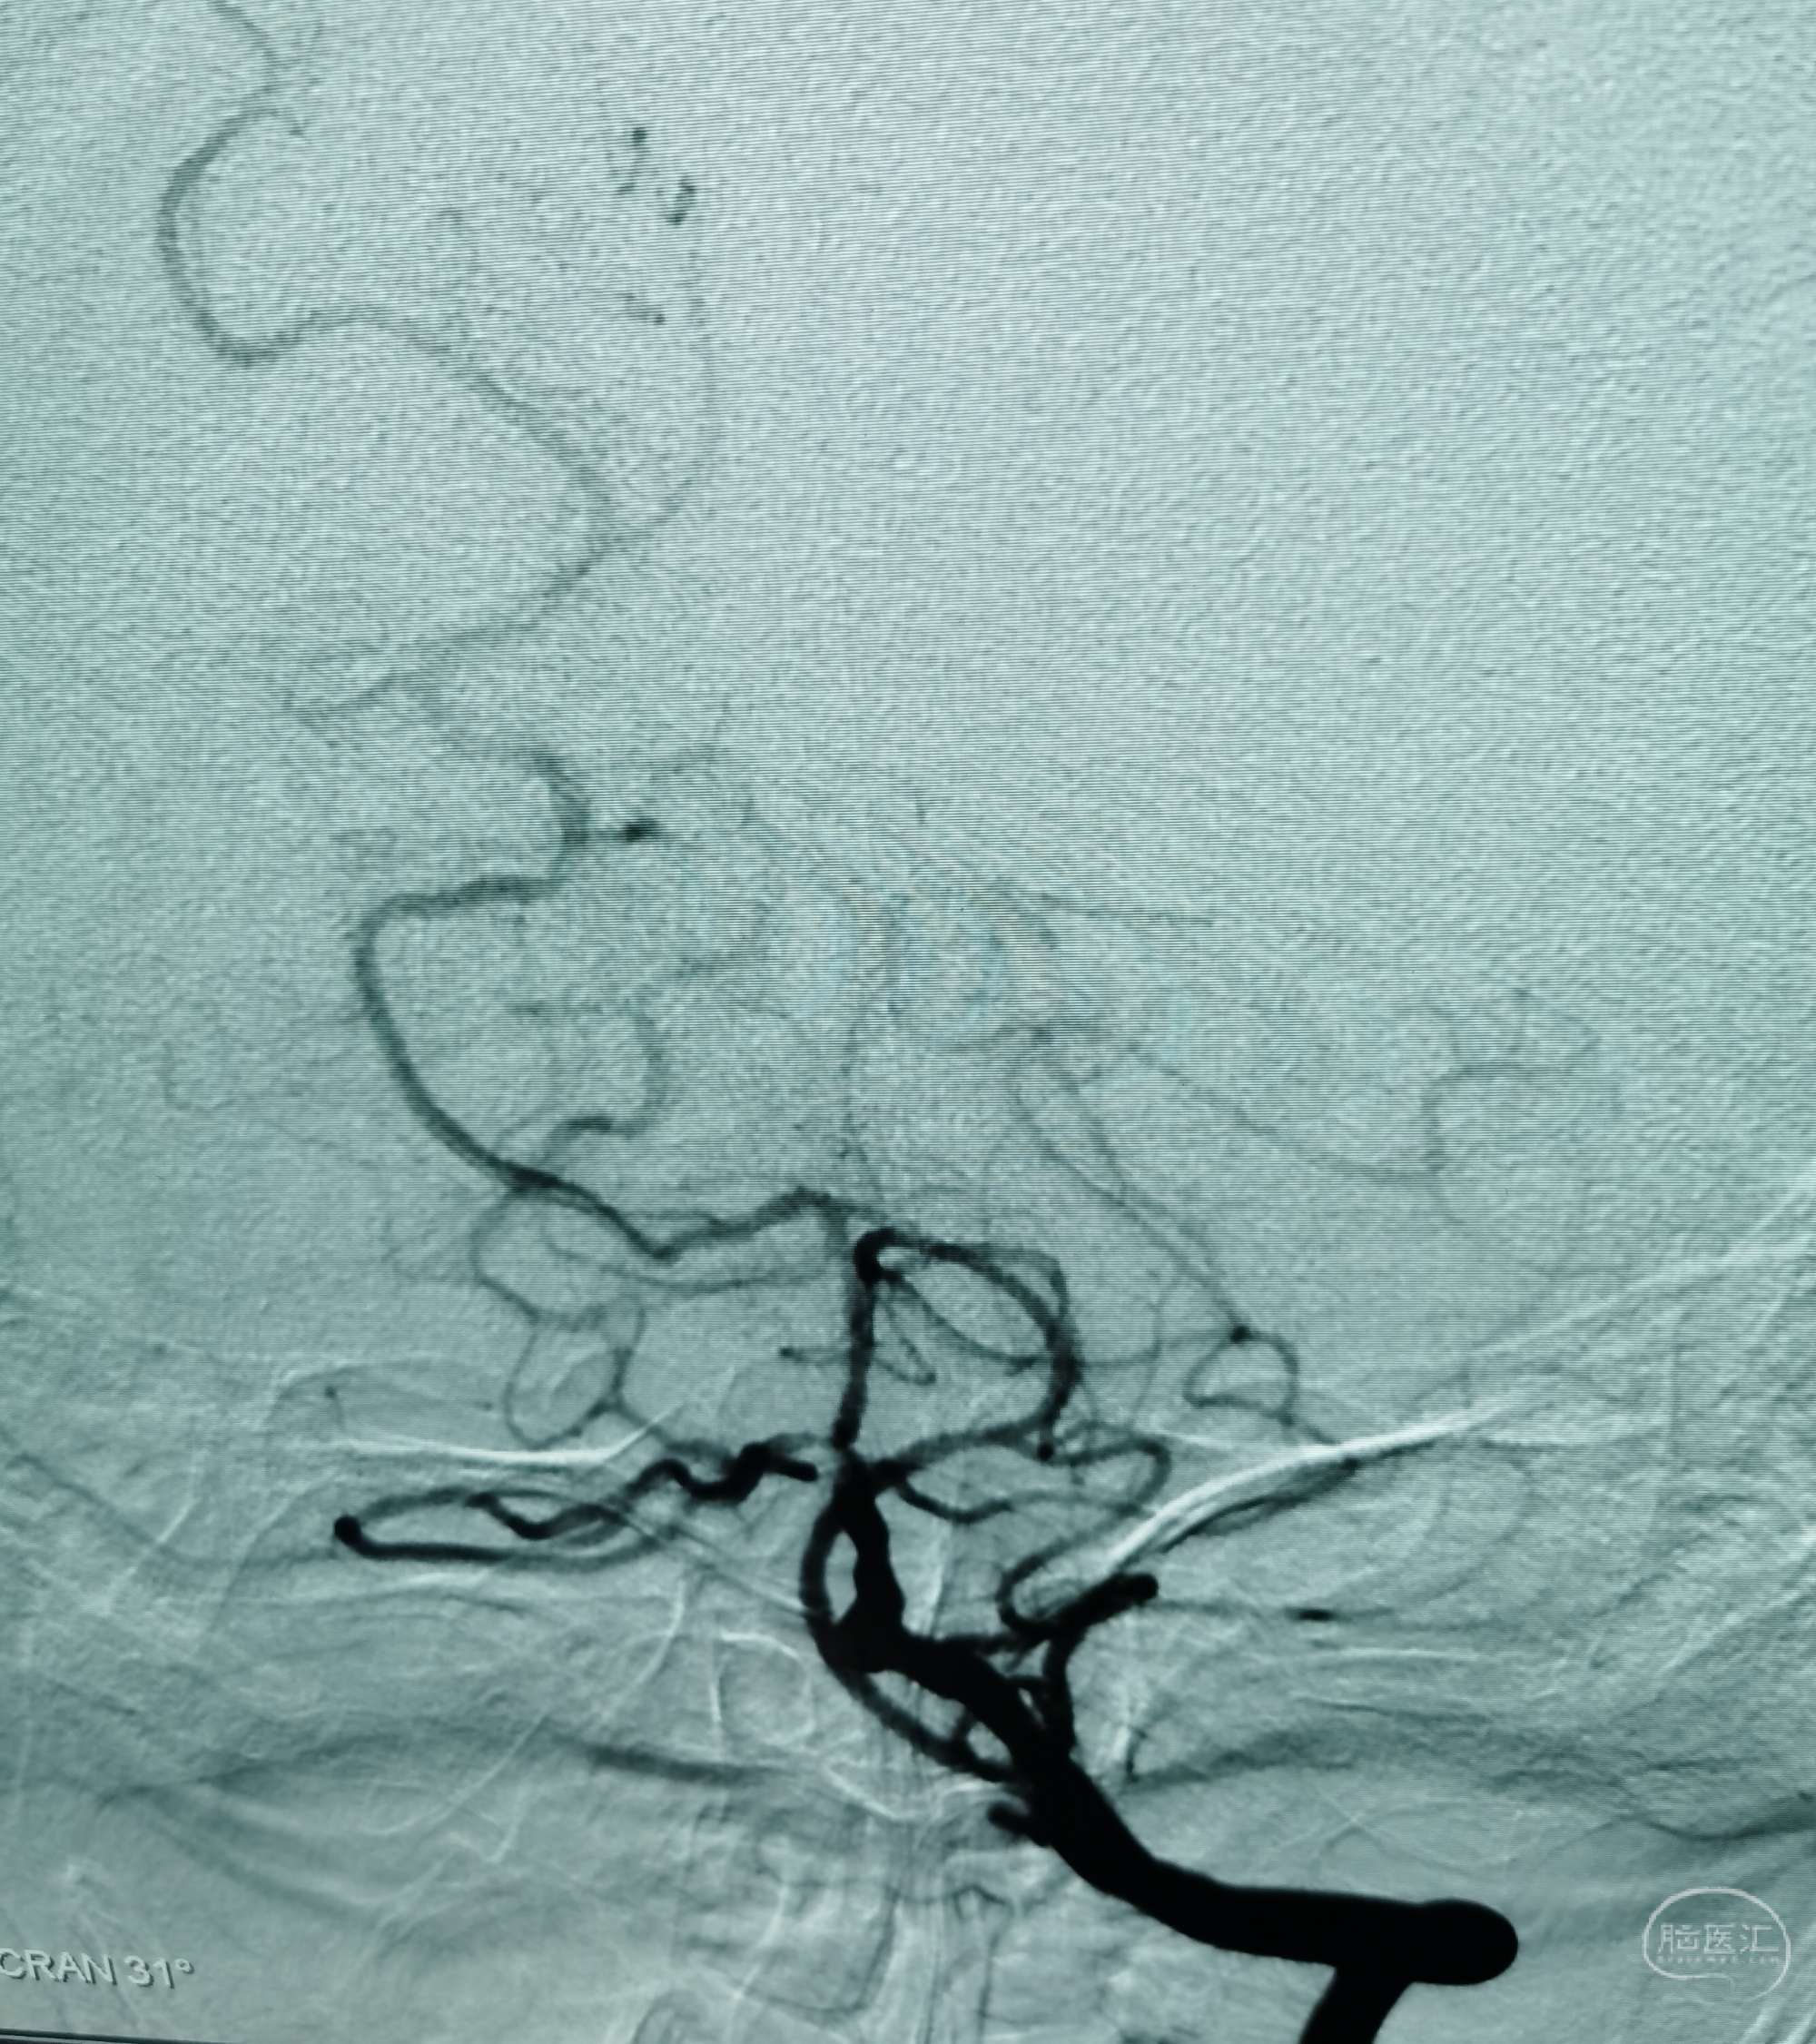

DSA:右侧大脑中动脉、大脑前动脉闭塞,烟雾样血管形成。

颞浅动脉未向颅内代偿。

行颞浅动脉-M4端侧吻合。

颞浅A一只吻合,一只种植。吻合14针。

荧光造影示:吻合桥动脉通畅。